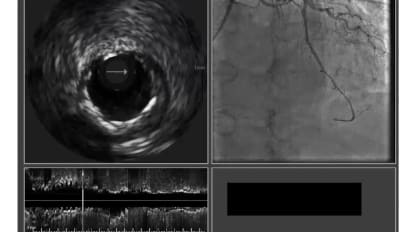

The current COVID-19 with patient care crisis: how are cardiologists and cath labs dealing

Dr. Armstrong review's some of latest ACC/SCAI guidance and recommendations regarding patient care in light of today’s evolving COVID-19 situation as well as his experience at a VA facility. There will be discussion with attendees on how their facilities and practices are dealing with this challenging new environment.